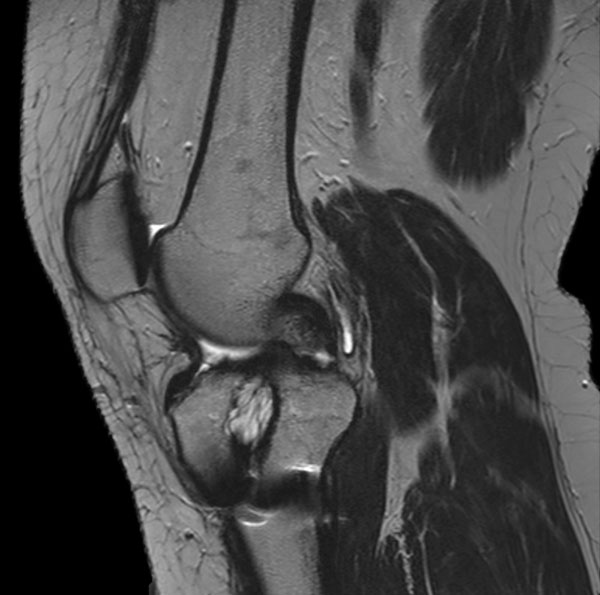

Sagittal T2w TSE

Sagittal T2w TSE (MARS)